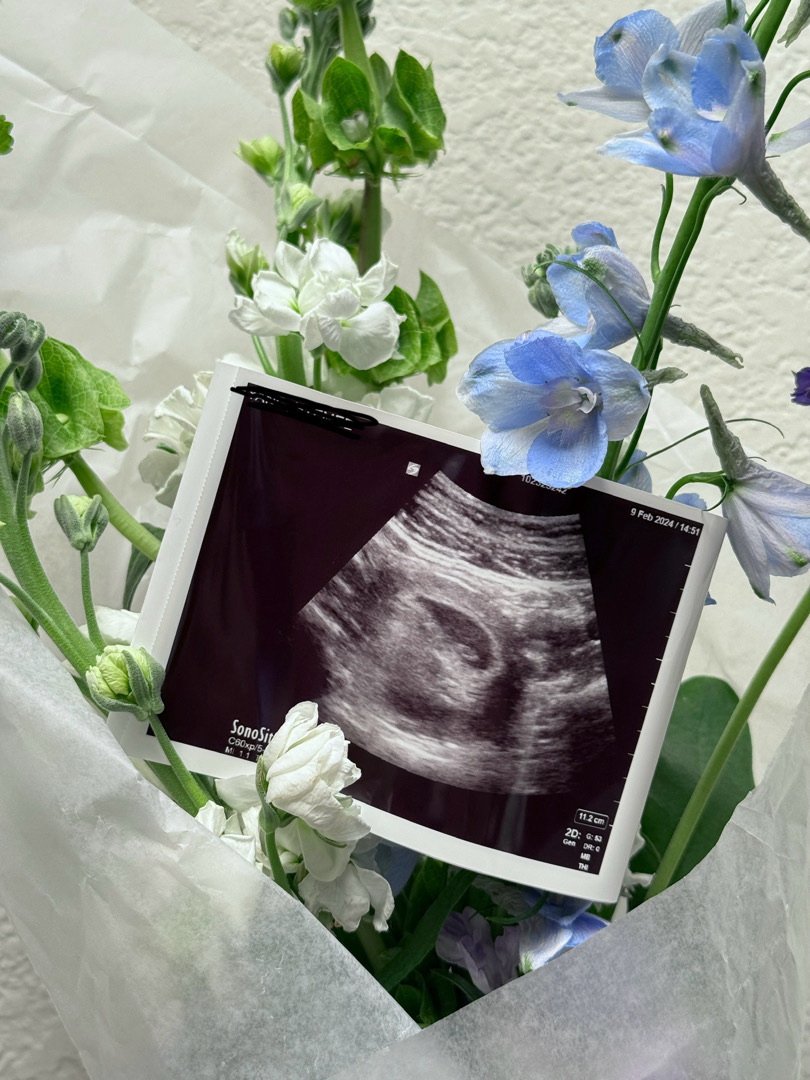

저도 드디어 첫 초음파를 보고왔어요!

해외에 있다보니 임신 사실은 4주차 때 알았지만 현지 병원 시스템상 7주차 지나야 병원 방문이 가능해서 드디어 지난주에 다녀왔습니당! ㅎㅎㅎ 불안한 마음 가득이었는데 그래도 실제로 보니 한 시름 덜었어요~~! ㅎㅎ 아직 심장소리는 못 들었지만 심장이 뛰는 모습을 보여주셔서 넘 신기했어요!! 다음 예약은 2주 뒤인데 부디 그 때까지 건강하게 잘 있어주길🙏🙏🙏